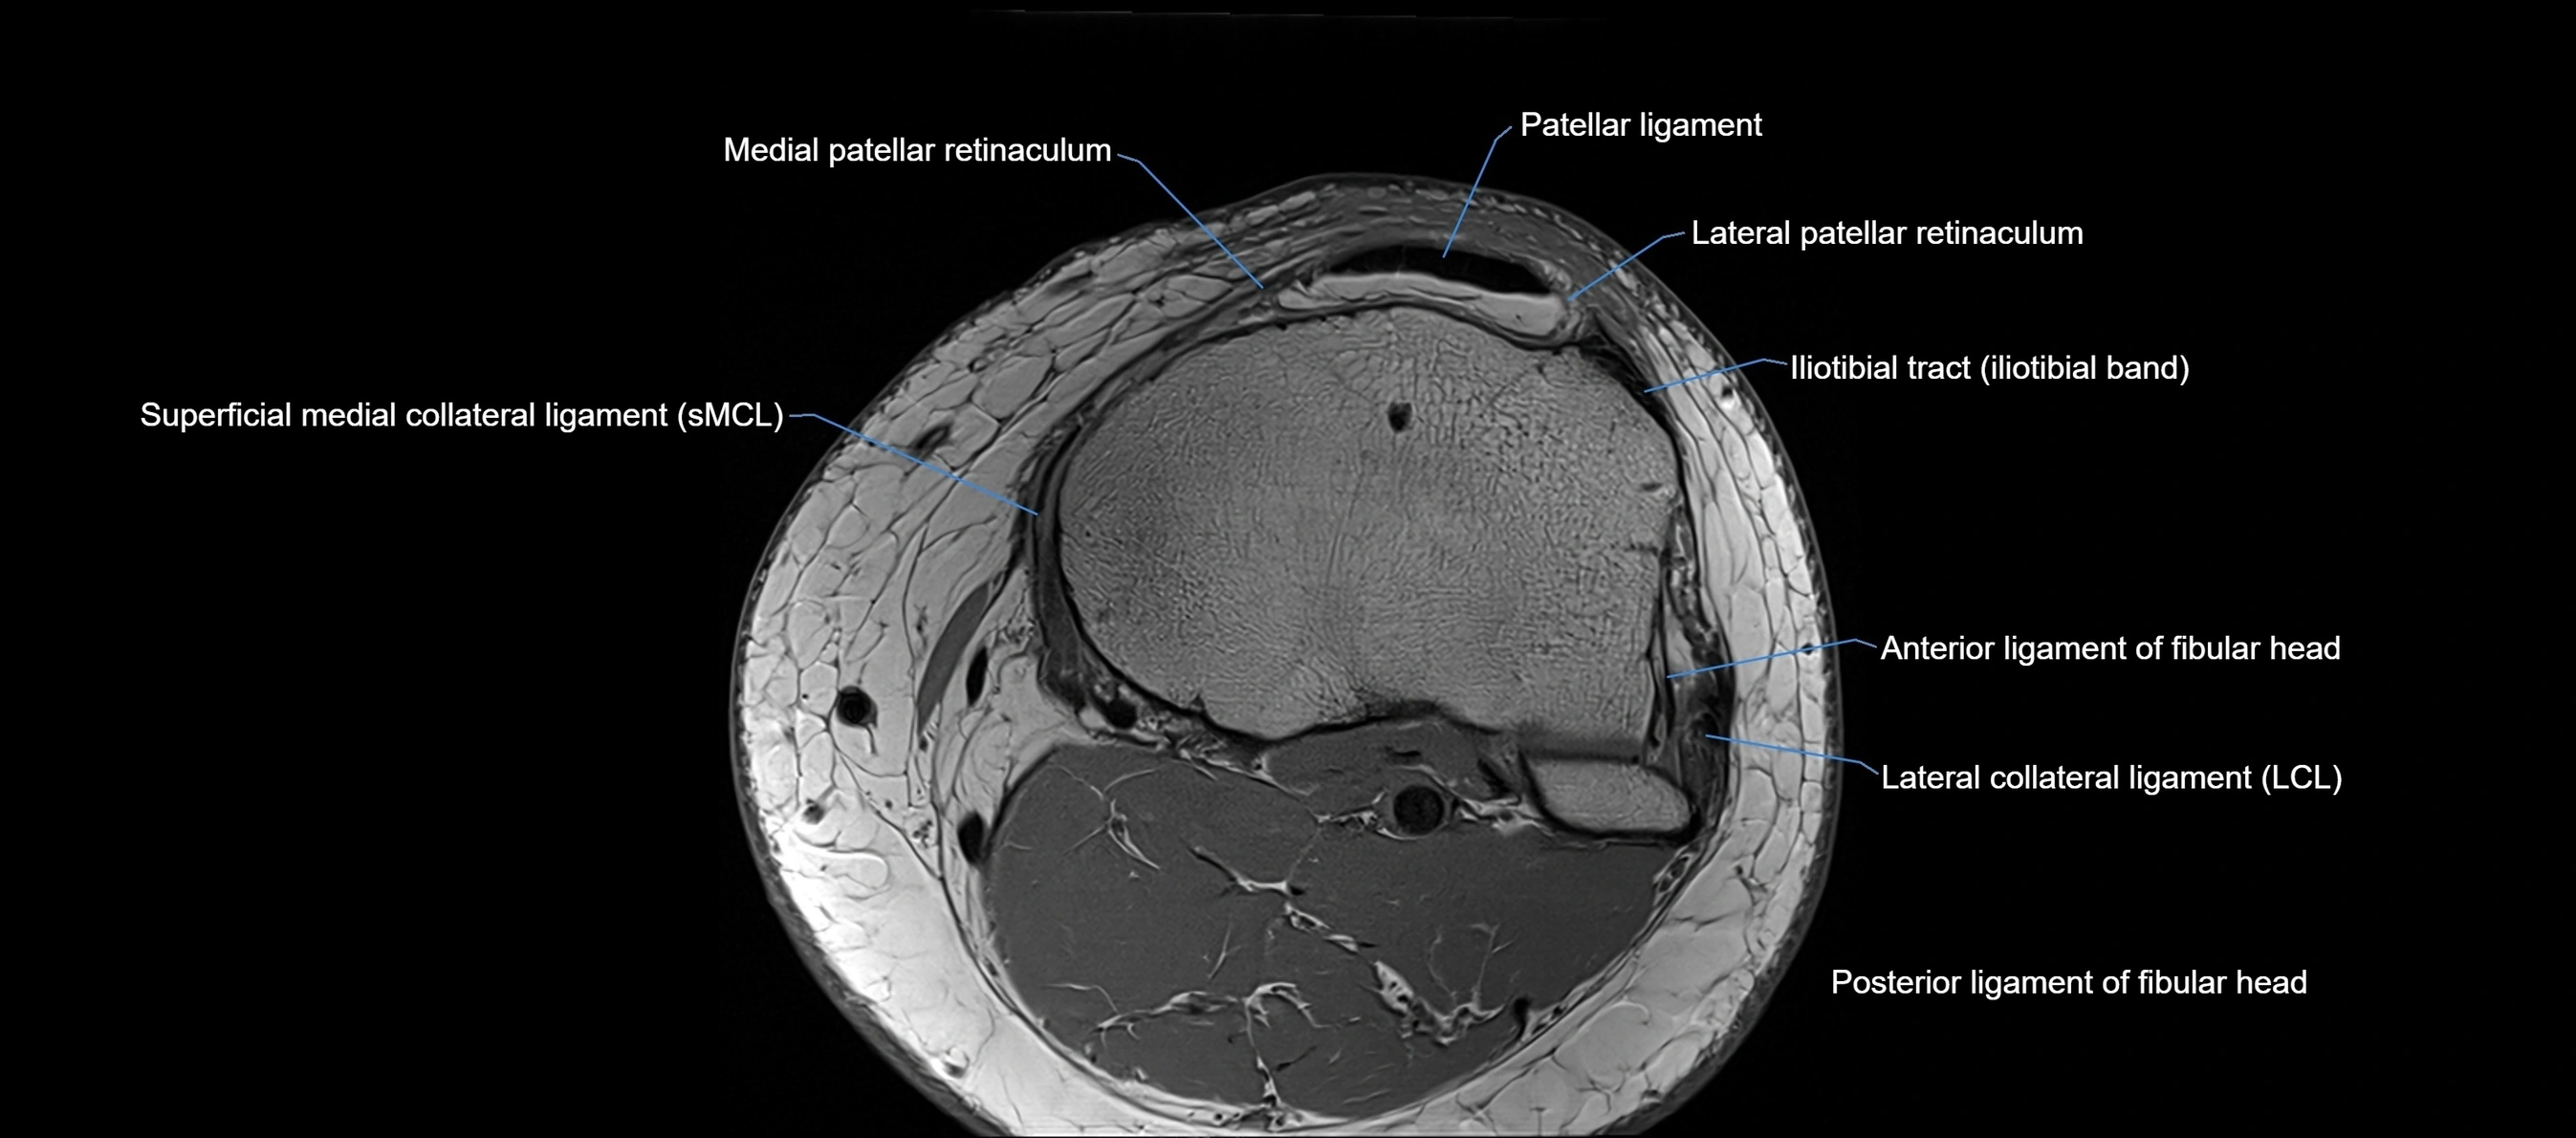

MRI images

image